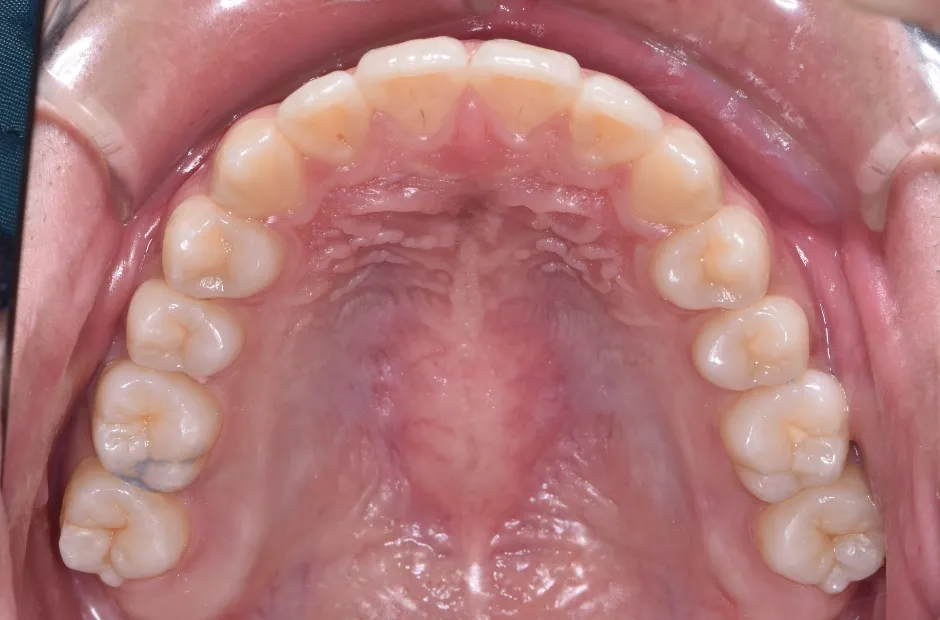

叢生

| 診断名・主訴 | 叢生 |

|---|---|

| 年齢・性別 | 43歳・女性 |

| 治療期間・回数 | 2年7か月 27回 |

| 治療に用いた主な装置 | 舌側矯正 |

| 抜歯部位 | 両顎4,4 |

| 治療費 | 100万円(税抜) |

| リスク・副作用 | 装置による違和感・疼痛・歯肉退縮・歯根吸収・虫歯のリスクなど |

治療後